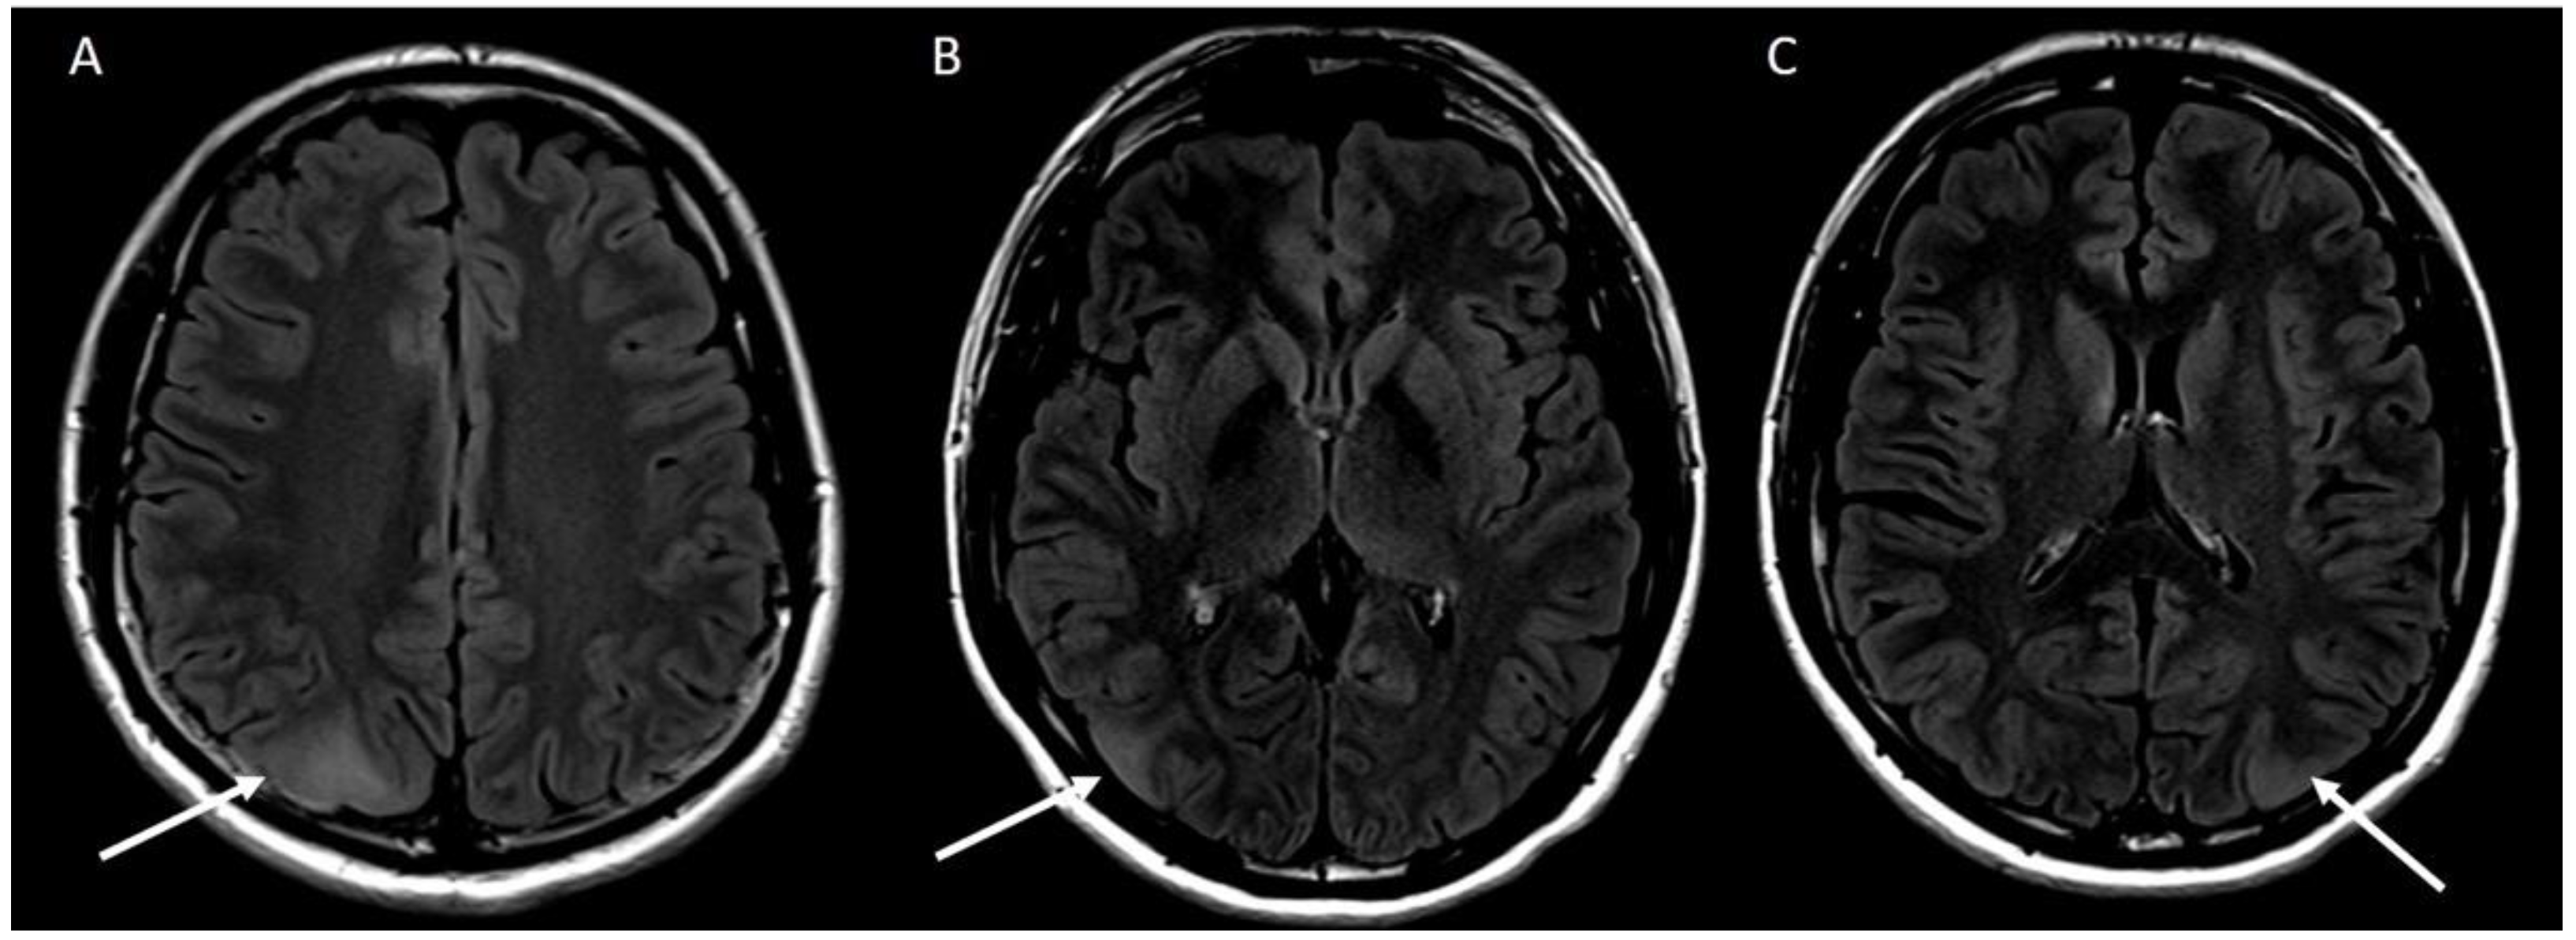

2. Case Report